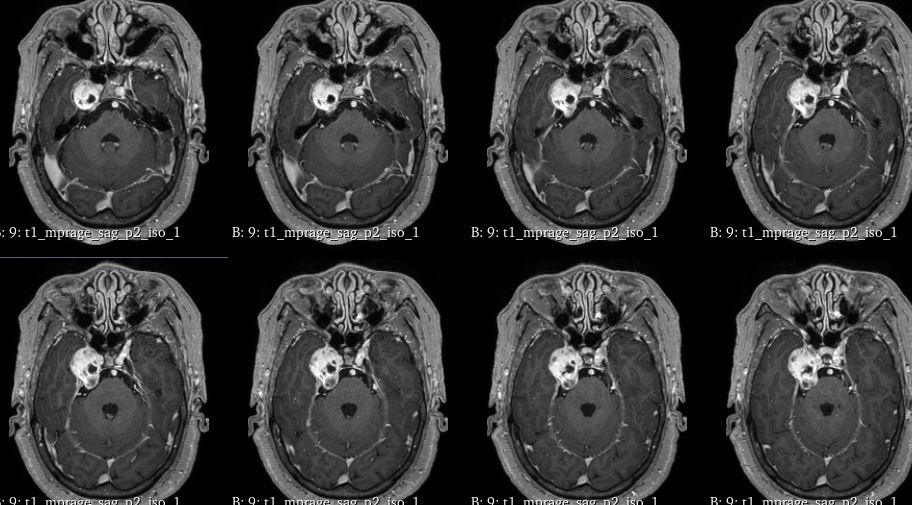

左额叶-胼胝体肿瘤卒中 侵犯对侧额叶 急诊开颅切除 镜下全切

脑肿瘤-胶质瘤

脑肿瘤-脑转移瘤

脑肿瘤-脑膜瘤

卢云鹤 关注

上海蓝十字脑科医院/同济大学附属脑科医院前天10:07 76阅读 0评论 1点赞 -